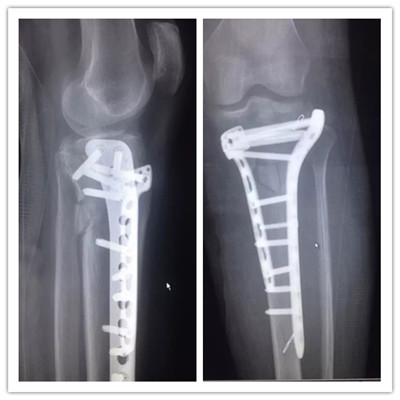

病例一:

患者小吳(化名),因車禍致左膝部受傷到廣安醫(yī)院就診,被診斷為“左脛骨平臺粉碎性骨折”,分屬第Ⅴ型,骨折移位明顯,碎裂嚴重,手術操作難度很大,殘留后遺癥幾率極高。廣安醫(yī)院院長劉志安通過“3D打印”進行“提前干預”,術前對鋼板放置的位置、數(shù)量及確定螺釘?shù)姆较蚝烷L度等,經(jīng)過反復多次的模擬手術,評估不同的手術方法,討論手術策略,制定出最適宜的個性化手術方案。

術后拍片